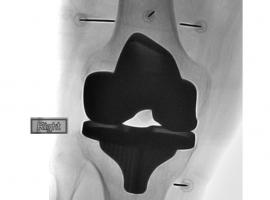

Actualité publiée le 02/02/2022ARTHROSE du GENOU : L'ostéotomie tibiale, alternative à l’arthroplastie totale

Actualité publiée le 03/01/2022